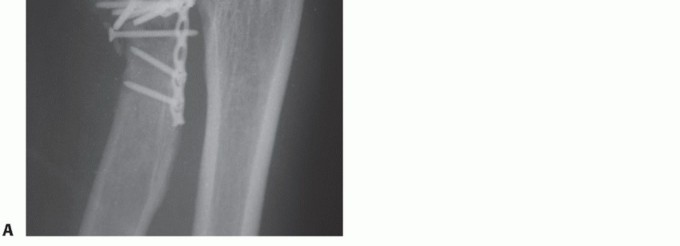

Serial x-rays are obtained to detect any loss of reduction at immediate postoperative, 2 weeks, 6 weeks, and 3 months, until healing is achieved (FIG 12).

- FIG 12 • Postoperative x-rays showing anatomic reduction of the radial head fracture. The Biotrak screws are radiolucent. Note that anchor holes are seen at the crista supinatoris where the lateral ulnar collateral ligament (LUCL) and annular ligament complex are repaired.

Symptomatic hardware may require secondary removal (FIG 13). Infection

FIG 13 • A. Oblique radiograph demonstrating prominent hardware limiting forearm rotation. B.*

Loss of reduction Nonunion (FIG 14)

- FIG 14 • ORIF of radial neck fracture that went on to nonunion and avascular necrosis.